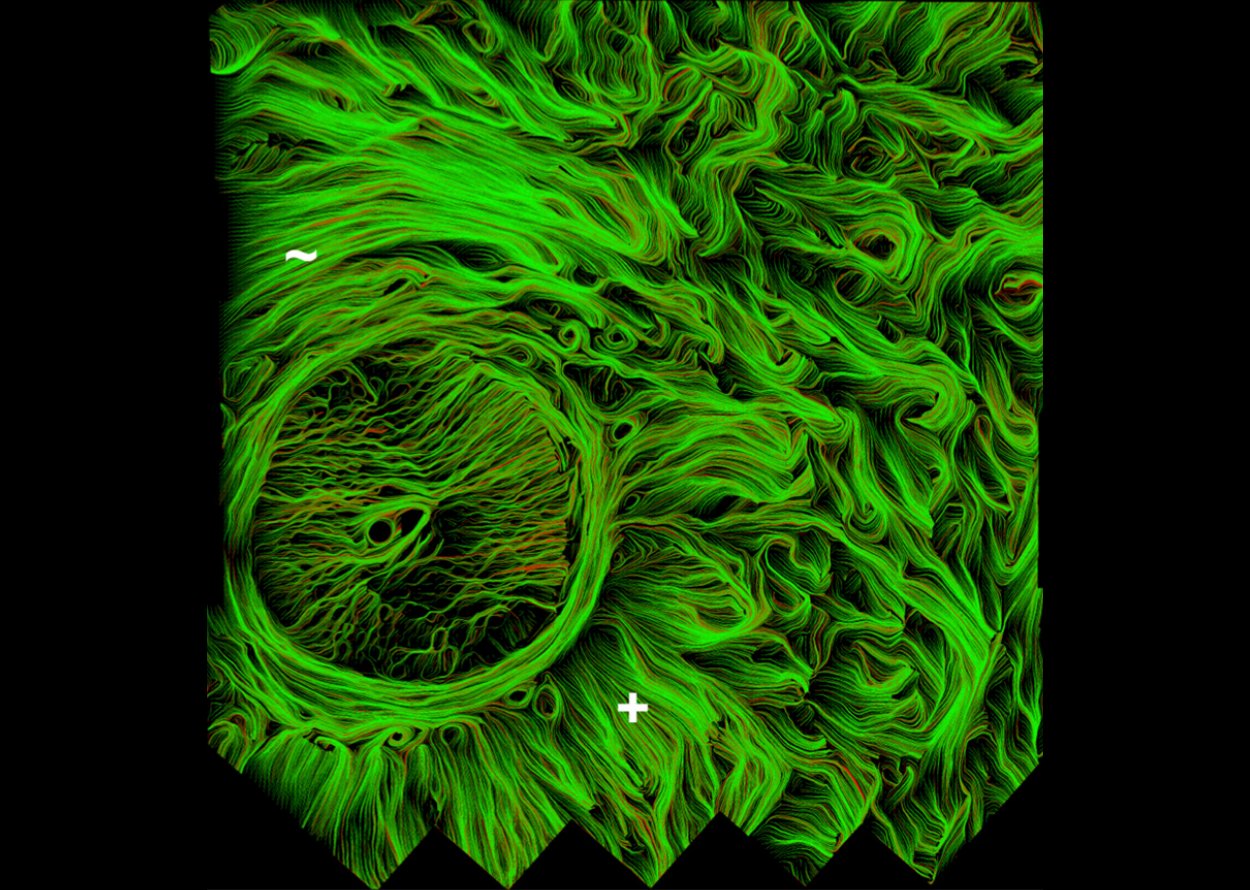

• Real-time imaging of optic nerve head collagen microstructure and biomechanics using instant polarized light microscopy

• PY Lee, B Yang, Y Hua, S Waxman, Z Ziyi, F Ji, IA Sigal

• Experimental eye research, 217, 109867, April 2022.

image